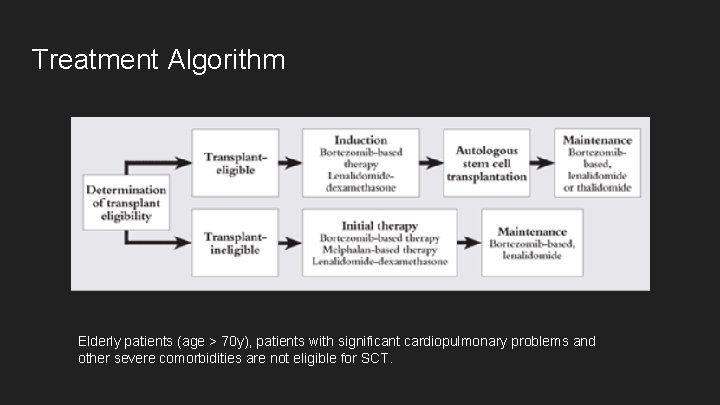

Treatment Algorithm Elderly patients (age > 70 y), patients with significant cardiopulmonary problems and other severe comorbidities are not eligible for SCT.